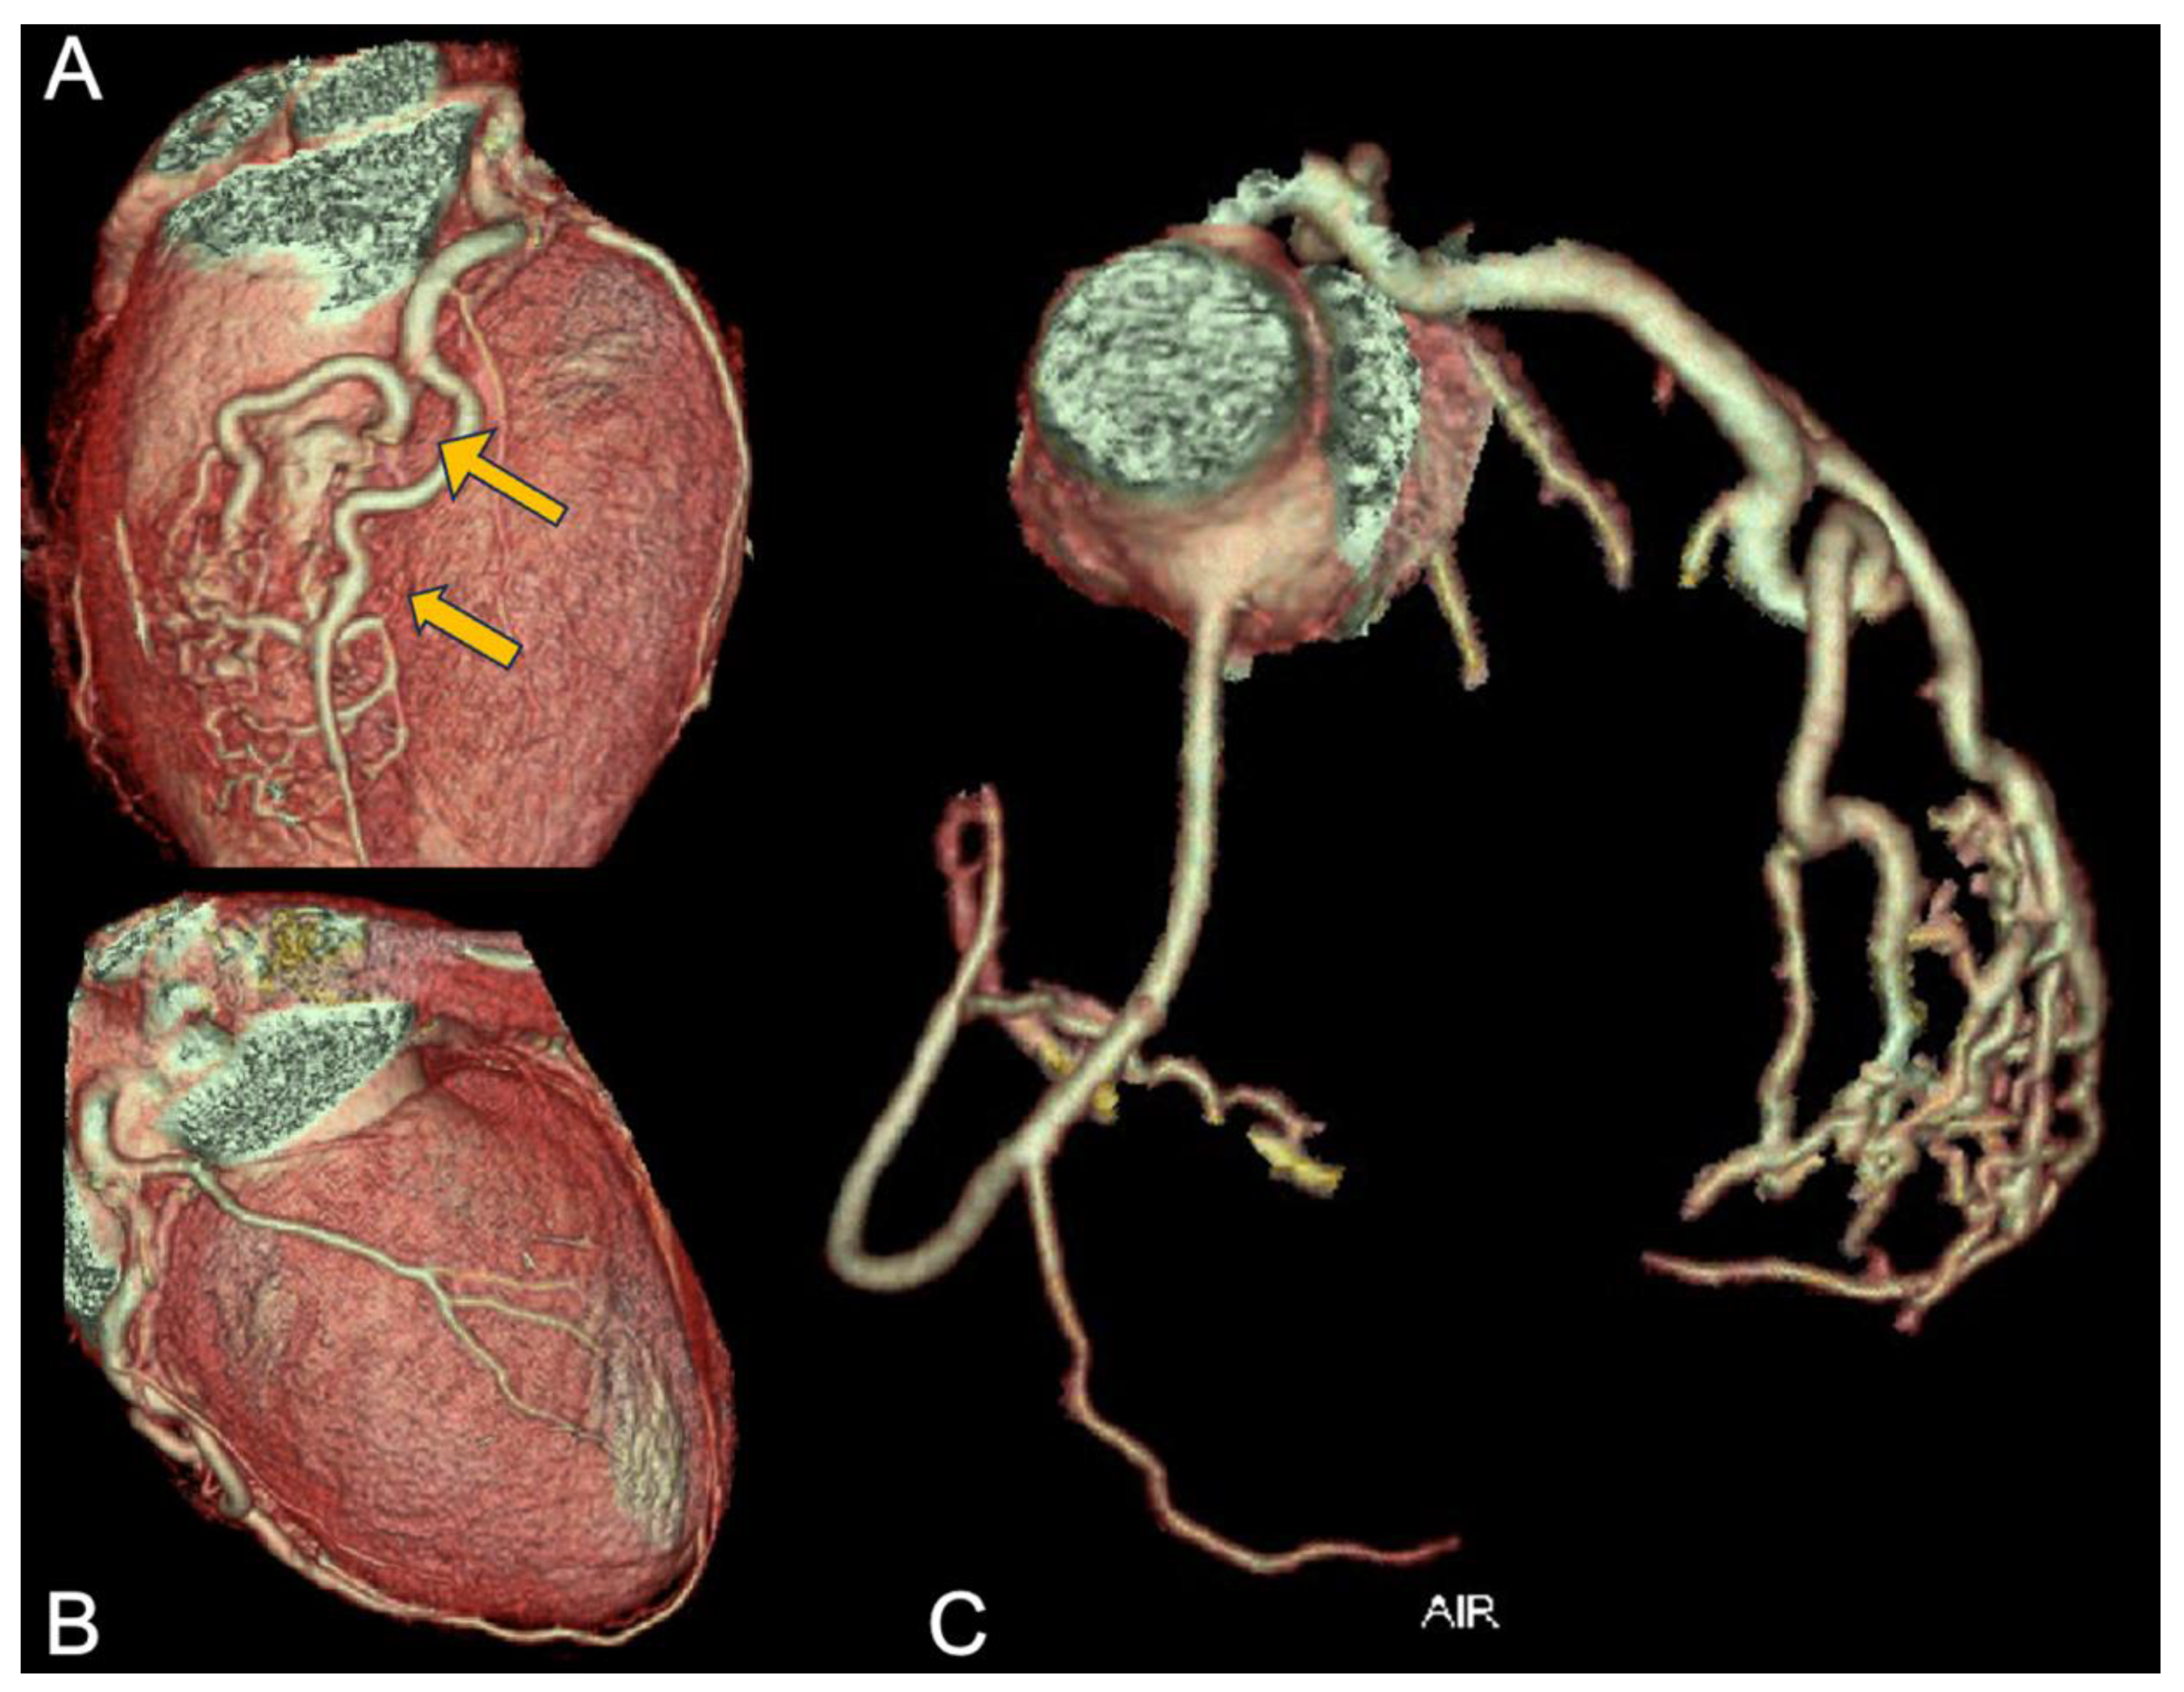

3.1. Case 1: Anomaly of the Right Coronary Artery Origin Presented as Cardiac Arrest

3.5. Case 5: Common Origin of Coronary Arteries from Left Valsalva Sinus with Interarterial Course